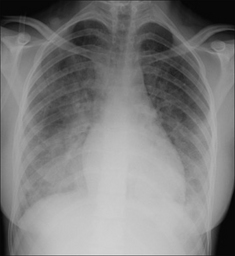

image

Figure 28.4 Acute dyspnoea. Left dome of the diaphragm appears to be high. Apply Golden Rule 3—you only look for what you know. Note the inferior displacement of the stomach air bubble. CXR conclusion—large subpulmonary effusion, not an elevated dome of the diaphragm (See p. 82).